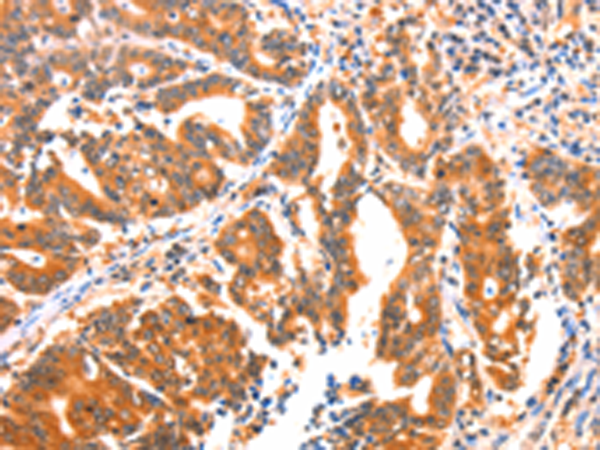

分类: 科研抗体货号: P04606别名: DIP; MIZ; MIZ1; SIZ2; ARIP3; PIASX; ZMIZ4; PIASX-BETA; PIASX-ALPHA应用: IHC反应种属: Human, Mouse